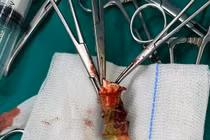

Sau 1 tháng xuất hiện ho, ngứa cổ... người đàn ông 65 tuổi đã được các bác sĩ gắp ra con đỉa dài hơn 5cm. Khi đỉa hút no máu, kích thích gây ho và có thể gây nhiễm khuẩn đường hô hấp dưới nguy hiểm đến tính mạng.